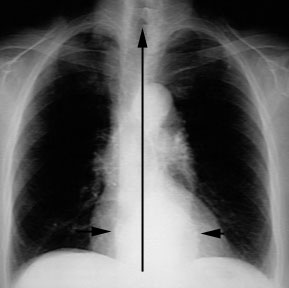

If the mediastinal density crosses mid-line most likely it is hiatal hernia